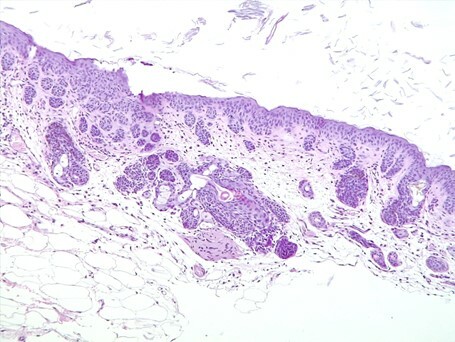

L’aspect histologique est tout à fait particulier, dominé par la présence de myriades de bourgeonnements ronds à amiboïdes de kératinocytes en provenance de la couche basale de l’épiderme et des infundibula. Au sein de ces bourgeonnements les kératinocytes montrent un rapport nucléo-cytoplasmique élevé avec un cytoplasme peu abondant et pâle et un noyau proéminent : aspect de cellules dites « basaloïdes ». Pour autant on n’observe ni atypies, ni perte de polarité, ni apoptose des kératinocytes. Le derme quant à lui est pâle, « myxoïde » avec la présence régulière de fibroblastes fusiformes sans atypies. Les glandes sébacées sont présentes et d’aspect normal. On n’observe enfin pas d’inflammation ou d’agents pathogènes figurés.

Aspect histologique de la peau. Notez les multiples bourgeonnements de cellules « basaloïdes » dans le derme superficiel et moyen. Notez également l’aspect pâle, cellulaire et « myxoïde » du derme

Le différentiel histologique est assez réduit. Chez un patient félin avec une telle dermatose multicentrique à extensive il faut évoquer théoriquement l’hypothèse d’une maladie de Bowen (carcinomes épidermoïdes in situ induits par un papillomavirus félin) en raison de cette prolifération de cellules basaloïdes en provenance de l’épiderme et de la partie haute des follicules pileux. Toutefois l’aspect global, l’absence d’atypie des kératinocytes et l’aspect du derme sont en défaveur de cette hypothèse. L’aspect histologique pourra donc être considéré comme caractéristique d’une entité rare récemment publiée : l’hamartome folliculaire basaloïde diffus.